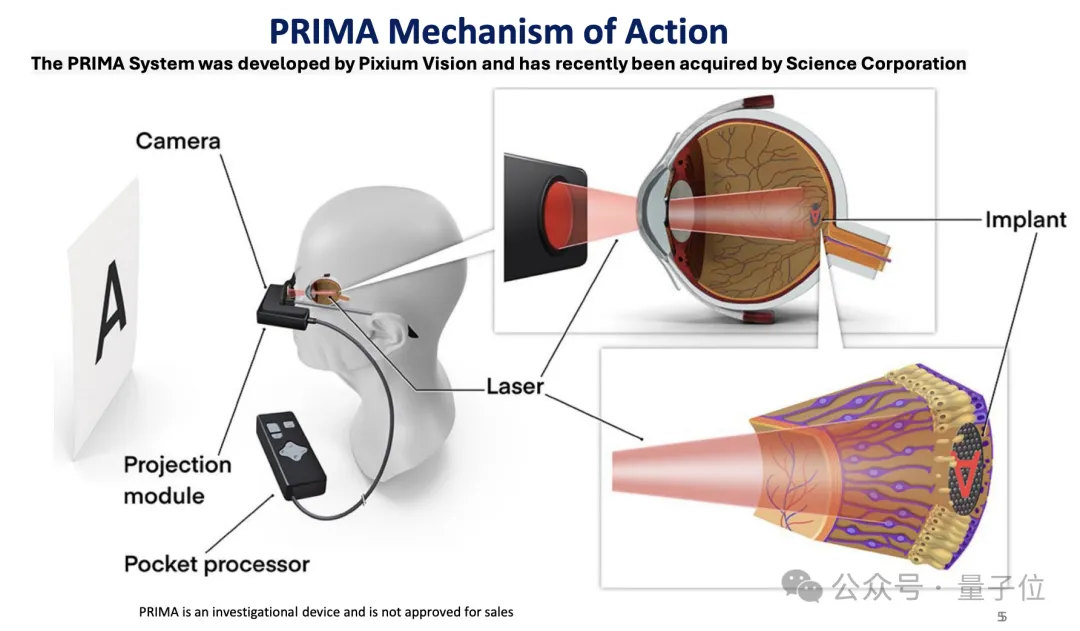

这款植入物名为PRIMA,大约2mm大小,需要通过手术植入视网膜,手术过程大约是80分钟。

植入完成后,PRIMA需要与配套的带有摄像头的眼镜一同使用。

PRIMA的原理是用摄像头捕捉视觉信息,并向芯片发射红外光图案,芯片接收到图案后,将光转换为电信号,并发送到大脑。

患者看到的图像和正常人仍有区别——由于向芯片发射的是红外光,患者看不到彩色,黑白也和真实世界相反。